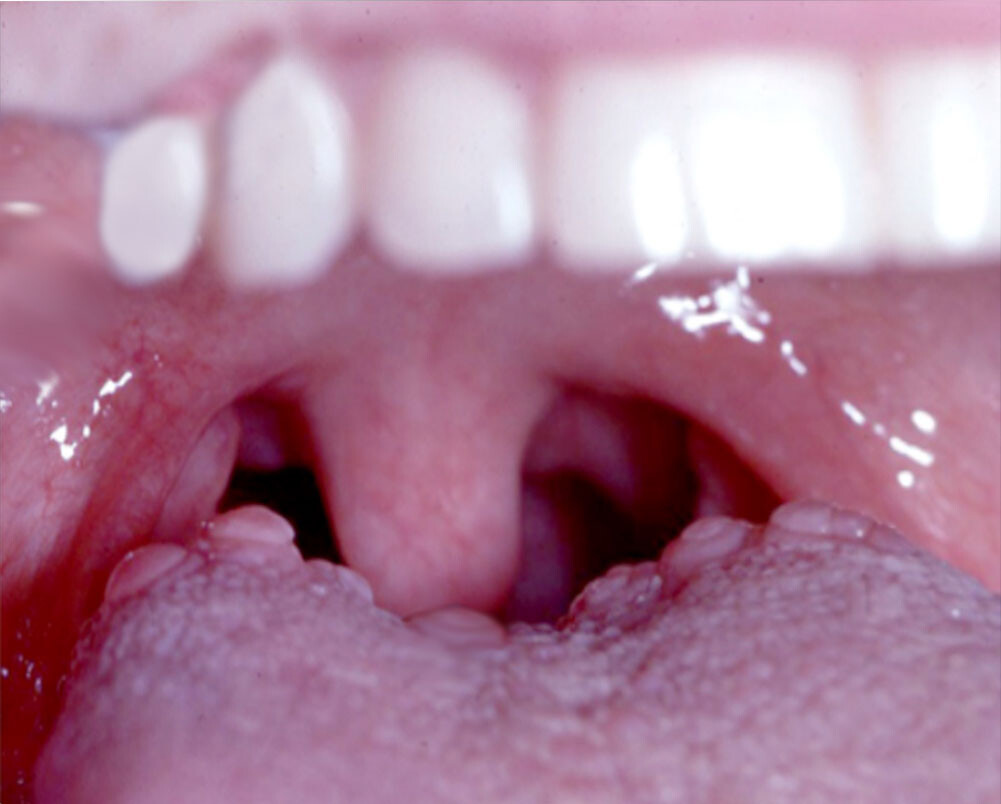

Bumps on the Back of the Tongue: Normal or Abnormal?

We don’t often think about our tongues, but they can actually be a marker of our overall health. The tongue’s appearance can change for many reasons, many of them not too serious. Have you ever noticed bumps on the back of your tongue? Often these bumps are caused by some type of oral infection. Find out what causes these bumps and when they are a cause for concern.

What Are Tongue Bumps?

The tongue is made up of muscles and the surface is covered with a mucous membrane. Typically, small bumps (also known as papillae) cover the surface of the back part of your tongue. Between the papillae are your taste buds that help you taste foods. Usually, these papillae are pretty unnoticeable. But sometimes, they become enlarged and can cause you pain. This can happen for many reasons.

What Are Common Causes of Bumps at the Back of the Tongue and How Can You Treat Them?

Some common reasons why you see large bumps at the back of your tongue include:

If your notice tongue bumps at the back of your mouth, it’s normal to be worried. But the good news is that most bumps on your tongue aren’t a cause for too much concern. That said, if your bumps are large, last for several weeks, or are exceptionally painful, don’t hesitate to get them checked. Your doctor or dentist can help you feel comfortable again in no time!